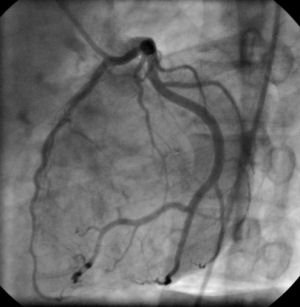

cardiac catheterization